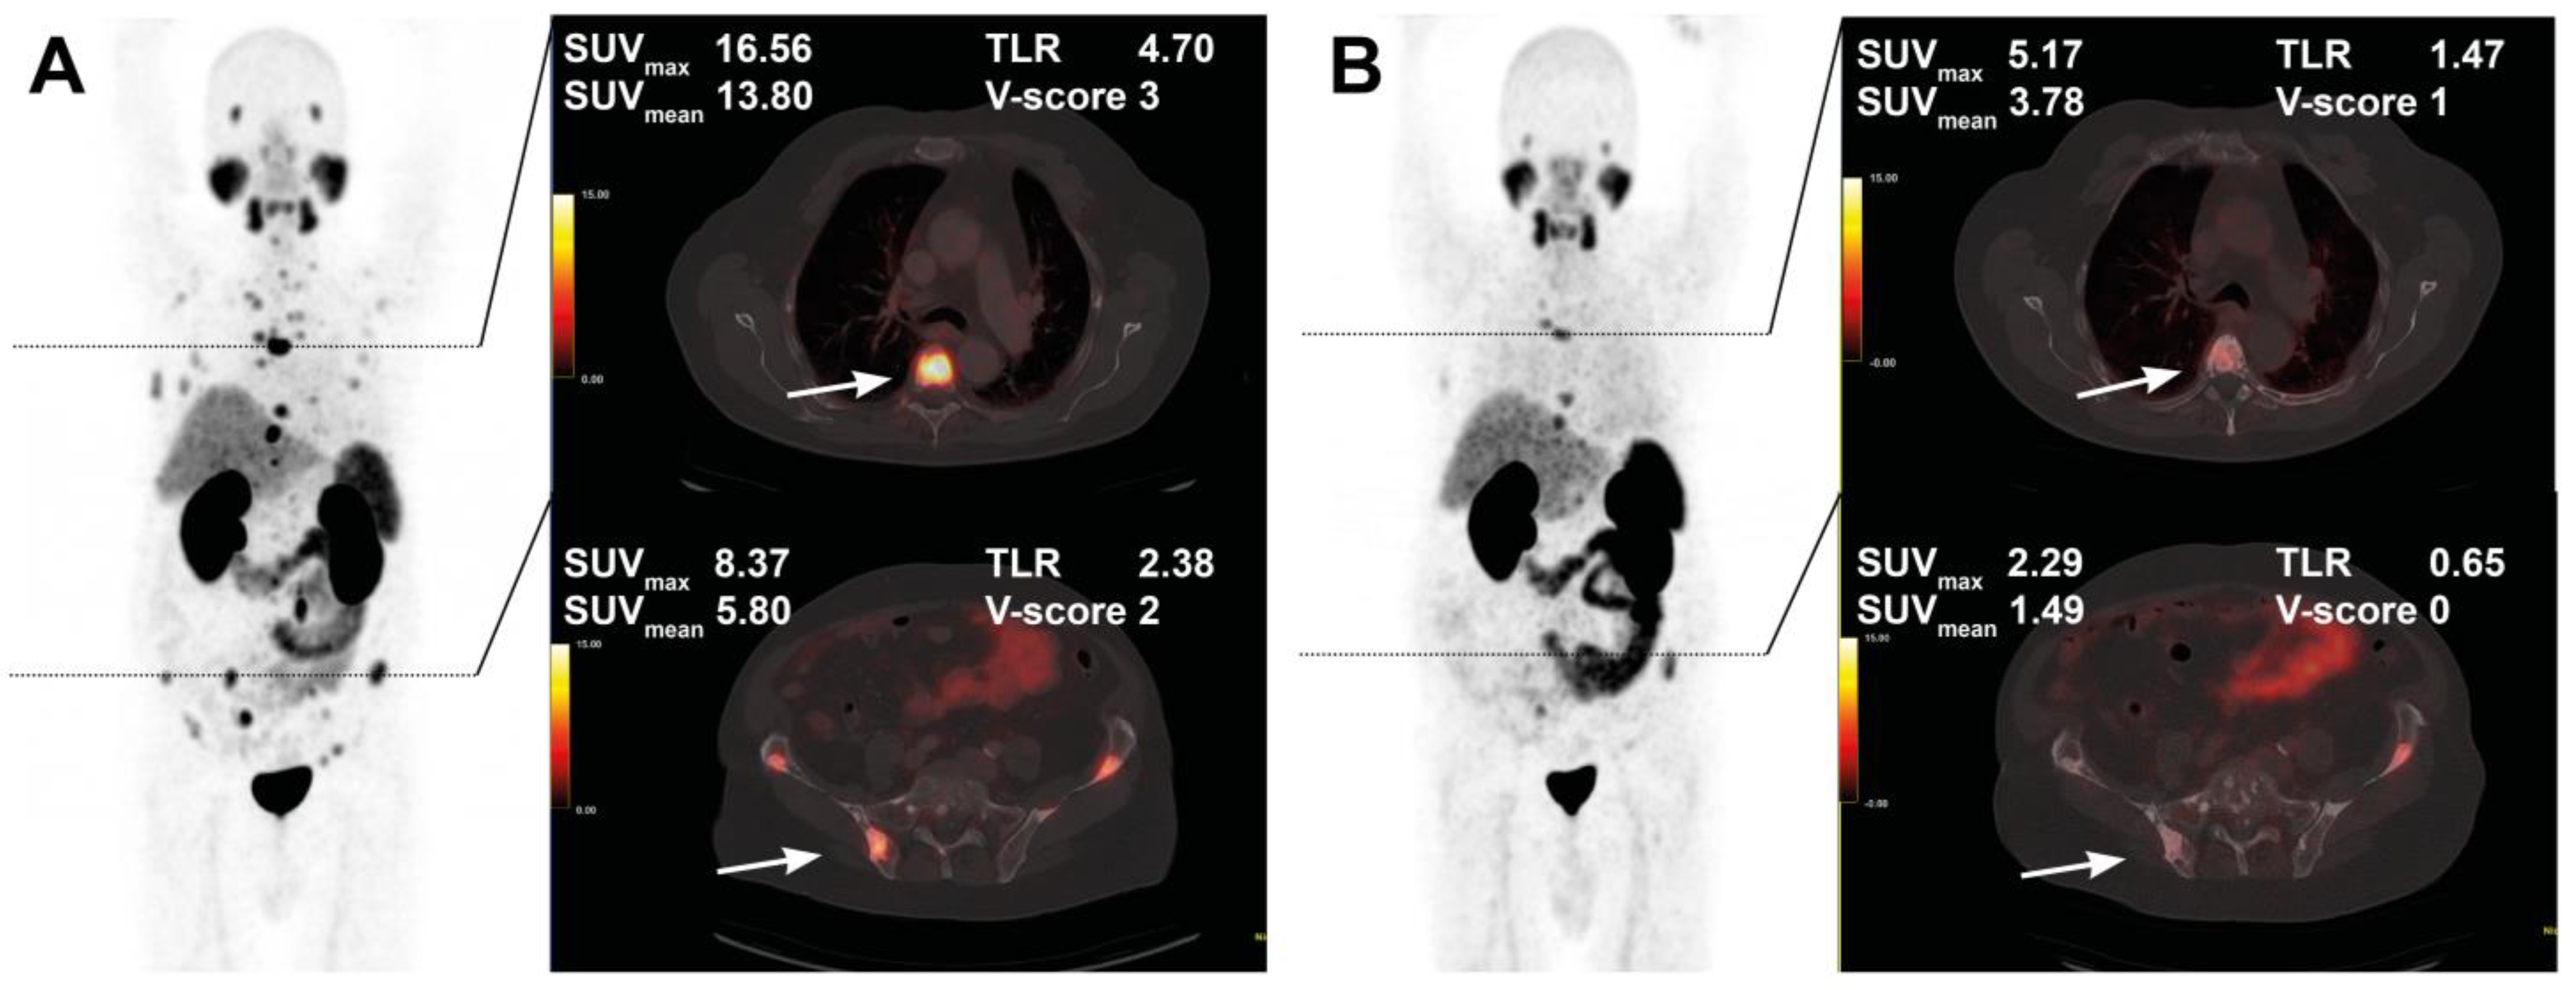

The course of all lesions per patient is depicted in Figure 3. In 11 patients showing lesion response in included baseline tumor sites, ≥2 new onset lesions on posttherapeutic imaging led to discontinuation of RLT. Examples of intraindividual lesion response on [68Ga]Ga-PSMA-11 PET/CT imaging are provided in Figure 4 and Figure 5.

Figure 4. Treatment response in a 76-year-old patient after 4 cycles of RLT with cumulative 32.0 GBq [177Lu]Lu-PSMA-617. Maximum intensity projection (MIP) images (left) with cross-section fusion images in a thoracic and pelvic plane at baseline (A) and after RLT (B). Lesions (white arrows) show response to RLT, with the upper lesion in the thoracic spine maintaining detectable residual activity.